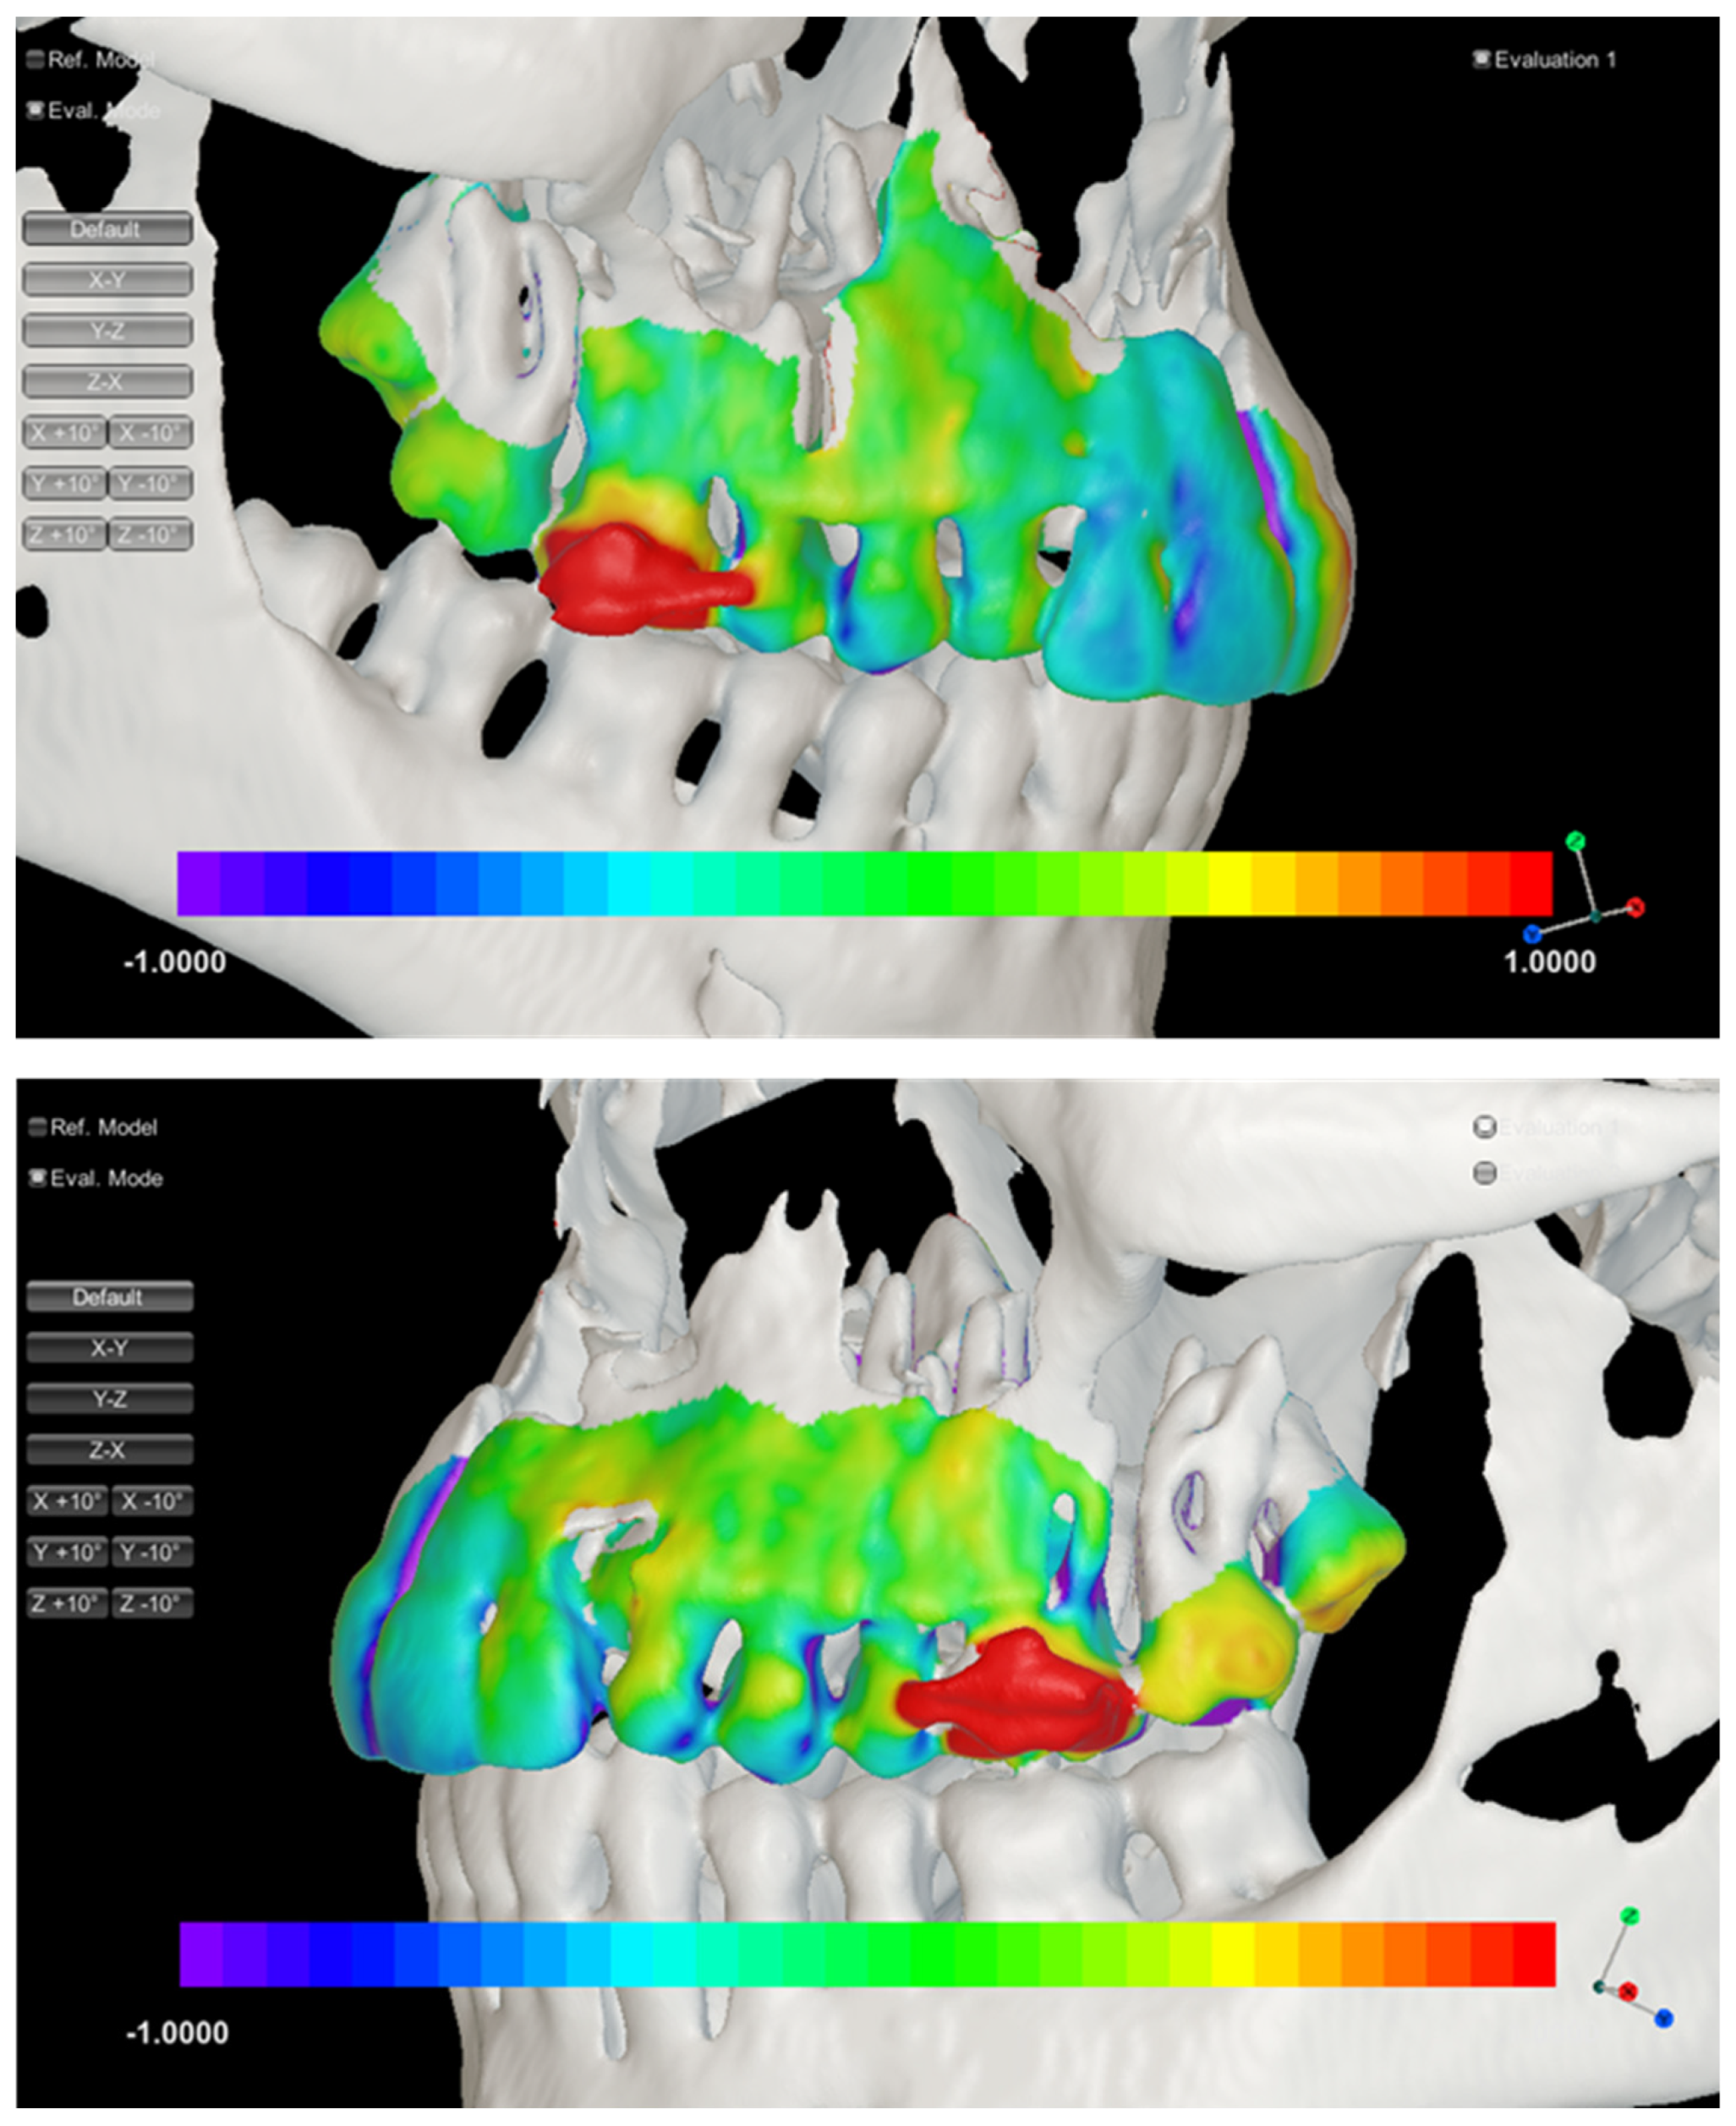

2.4. Three-Dimensional Visualization